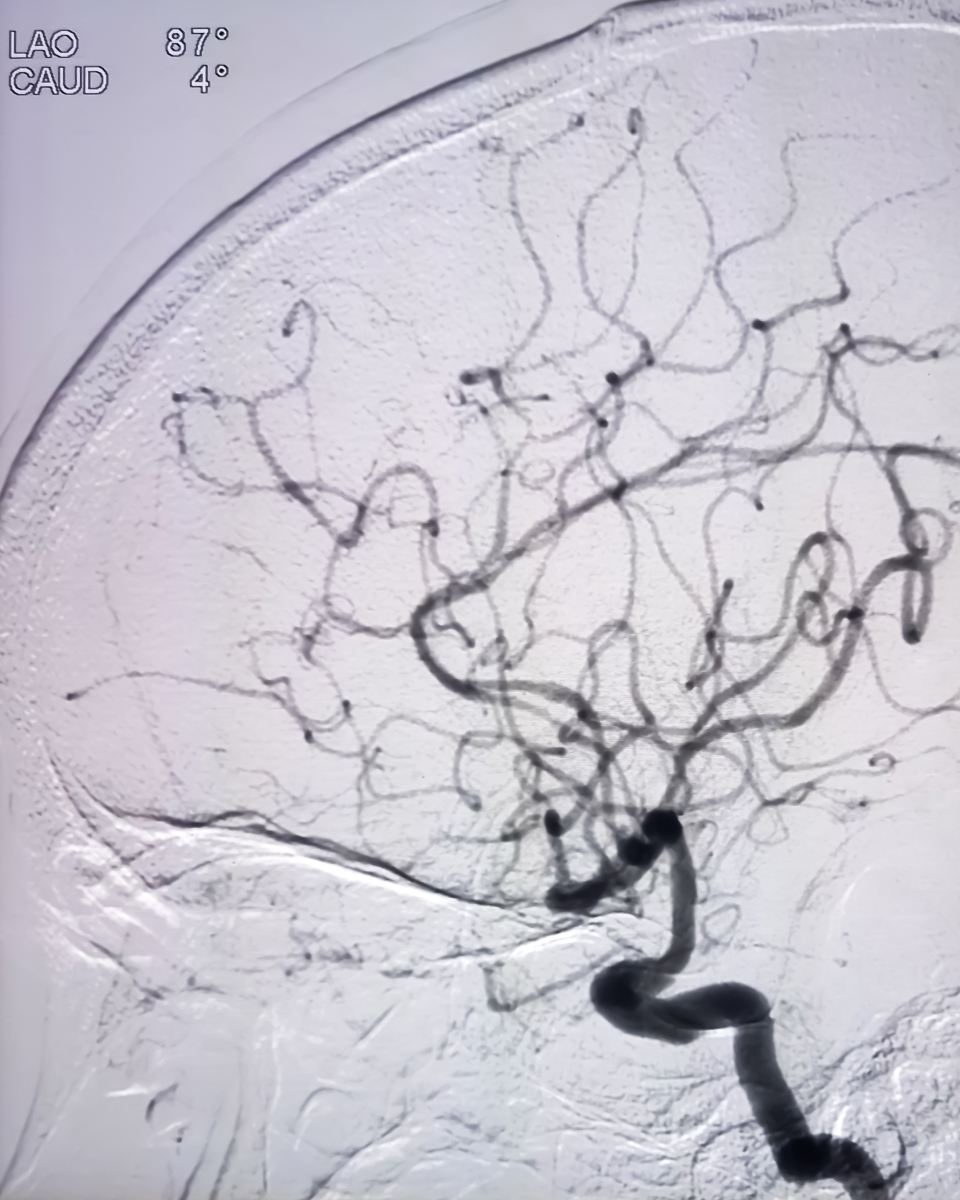

撮影法については、当初は連続フィルム撮影であったため、造影剤の入る前のマスクフィルムを白黒反転させて血管造影フィルムと重ね合わせることで骨部分を除去するマニュアルサブトラクション法が主流であったが、1990年ごろよりデジタルサブトラクション法(DSA)が登場してリアルタイムのサブトラクションが可能となり、血管構築の理解に極めて有用となった。その後回転撮影の進歩とともに、回転の各角度でサブトラクションを行う3D-DSAが開発され、三次元的把握が容易となっている。現在高解像度バイプレーン装置、IVR-CTおよびCone beam CTの一般化により、多面的多角的な画像情報が得られるようになった他、カラー表示により位相の変化を視覚化することも可能になった。また、造影剤も非イオン性造影剤の普及により血管刺激及び高浸透圧による合併症が減少した。

脳血管内治療は脳血管撮影を基本に行われるが、1927年にEgas Monizが発明したのとほぼ同時期に、我が国で名古屋大学初代外科教授である齋藤 眞が脳血管撮影を開発した。このため我が国では、脳血管撮影を脳神経外科医が主に担当するという流れができた。我が国では海外に比べて神経放射線の専門医が少ないという事情と、放射線治療や内科的治療など脳神経外科医がカバーする業務範囲が極めて広いことも、脳血管内治療の推進に脳神経外科医が大きく関与してきた背景にある。会員の約9割は脳神経外科医で、放射線科、内科医、救急医、その他の研究者などが参加している。欧米では神経放射線科医が主としてこの分野を開拓し、発展させてきたが、現在は主要国においても我が国と同じような構図になりつつある。一方、近年は急性虚血性脳卒中や頚動脈狭窄症に対する血管内治療が急増していることから内科(神経内科、循環器内科)や救急科からの参入が増えており、幅広い展開が期待されている。